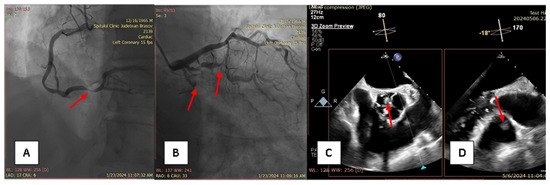

A 58-year-old male patient with multiple cardiovascular risk factors (high blood pressure, dyslipidemia, peripheral arterial disease, smoker) and a relevant family history (father had a myocardial infarction at age 56) with a history of pituitary adenoma surgery presented with persistent exertional dyspnea. TTE revealed a round, oval tumor attached to the pulmonary valve. The ejection fraction was estimated visually at 55%, with no segmental or global kinetic abnormalities and no signs of pulmonary thromboembolism (PE). The dyspnea persisted; therefore, the patient underwent coronary angiography, which revealed chronic occlusion of the circumflex artery, severe distal stenosis of the right coronary artery, and severe stenosis of the intermediate branch (Figure 1A,B). To accurately assess the tumor formation, the patient underwent cardiac MRI, which described a tumor formation (1.1 × 0.8 cm) as iso-/hypointense on T1-weighted sequences, mildly hyperintense on T2-weighted sequences, with no central enhancement but peripheral enhancement with gadolinium on delayed post-contrast sequences. These tissue characteristics supported the diagnosis of a papillary fibroelastoma (Figure 2A,B). Additionally, no other cardiac tumor structures were identified, and no signs of acute or chronic pulmonary embolism were detected. After obtaining the patient’s written consent and following discussions within the Heart Team, the patient underwent excision of the tumor formation from the pulmonary valve and coronary artery bypass grafting. Intraoperative transesophageal echocardiography (TEE) revealed a round, oval, mobile, well-defined tumor approximately 1.1 × 0.8 cm in diameter, attached to the surface of the right cusp of the pulmonary valve (Figure 1C,D). The tumor did not exert a hemodynamic impact on the valve, was not associated with pulmonary stenosis, and was accompanied by only mild pulmonary regurgitation. No other significant valvular pathologies were observed, and there was no echocardiographic evidence of PE. The surgical intervention was performed via sternotomy, under cardiopulmonary bypass with central cannulation: arterial in the ascending aorta and venous in the right atrium. Cardiac arrest was achieved using Calafiore cardioplegia. Initially, the distal coronary anastomoses were completed, followed by a longitudinal incision of approximately 4 cm in the pulmonary trunk to access the tumor. The tumor was friable, mobile, measuring approximately 1.1 × 1.0 cm, and attached to the pulmonary artery side of the right cusp of the pulmonary valve (Figure 3A). It was completely resected along with a small portion of the right pulmonary cusp that included its implantation base. Since only a small amount of valvular tissue was resected, valve repair was successfully performed using a continuous suture with 5.0 Prolene, Ethicon Inc., Cornelia, GE, USA, without the need for autologous pericardium or other biological materials (Figure 3B–D). Subsequently, the proximal coronary anastomoses were completed. No residual pulmonary regurgitation was detected. No other tumor formations were detected intraoperatively. The macroscopic appearance of the tumor was similar to a sea anemone when placed in serum (Figure 4A). The diagnosis of papillary fibroelastoma was confirmed by histopathological analysis (Figure 4B,C). The postoperative course was favorable and without complications, and the patient was discharged without further complaints of dyspnea.

Figure 3. (A)—intraoperative aspect of the papillary fibroelastoma; (B)—repair of the right cusp of the pulmonary valve; (C,D)—transesophageal echocardiography, postoperative aspect with no residual regurgitation.